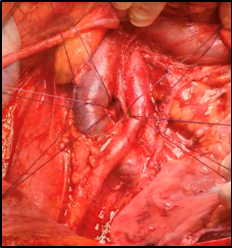

- Exploración y disección

El paciente es posicionado en posición decúbito supino, con las extremidades superiores en abducción forzada. Se realiza instalación de sonda nasogástrica y sonda vesical. Se realiza una incisión media desde el apéndice xifoides hasta la sínfisis del pubis; habitualmente se prolonga la incisión en cruz, por sobre el nivel del ombligo, y se fijan los vértices. Se seccionan los ligamentos redondo y falciforme y se realiza una exploración de toda la cavidad abdominal. Se accede al retroperitoneo, realizando una incisión del peritoneo parietal, mediante la maniobra de Cattell-Brasch, liberando el parietocólico derecho por la fascia de Toldt hasta ángulo hepático del colon y liberación a medial hasta ángulo de Treitz. Se realiza una maniobra de Kocher, rechazando duodeno y cabeza de páncreas a medial. El intestino delgado se cubre con compresas y se rechaza a cefálico, fuera del campo quirúrgico. Después de esta exposición se diseca la arteria aorta (AA) y vena cava (VC) inferior, sobre el nivel de bifurcación donde se realizará la canulación (Imagen 1). En este punto es importante identificar variantes anatómicas, como vasos renales accesorios, que hasta en un 3% pueden emerger incluso de la arteria iliaca, en cuyo caso es necesario modificar el sitio de canulación. Luego se procede a disecar, ligar y seccionar la arteria mesentérica inferior. Se libera riñón derecho e izquierdo, por plano de Gerota, requiriendo ventana de mesenterio a izquierda. En esta etapa no se debe manipular el hilio renal. Se diseca VC sobre el hilio renal y se deja controlada con sutura gruesa. Se diseca, liga y secciona la arteria mesentérica superior. Se diseca el hilio hepático, y se liga la vena porta. Se disecan y seccionan los pilares del diafragma, y se controla la AA infradiafragmática.

Fig. 1. Visión del retroperitoneo, con vena cava rechazada a la derecha y aorta y su bifurcación hacia la izquierda